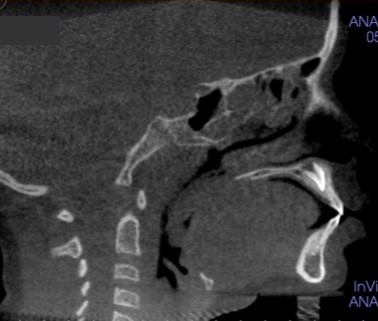

Airway dysfunction can impact much more than sleep. Children with restricted airways may struggle with focus, delayed speech, poor academic performance, or behavioral challenges that mimic ADHD. These symptoms often go unnoticed during standard checkups. That’s where a pediatric airway dentist steps in, using 3-dimensional diagnostic imaging, physical evaluations, and sleep assessments to identify root causes early.

If you are searching for a pediatric dentist near Westwood/Century City, look for someone who understands the connection between oral structure and airway health. Conditions such as tongue ties, narrow dental arches, or malocclusion can impact more than just a smile; they affect how your child breathes and sleeps.